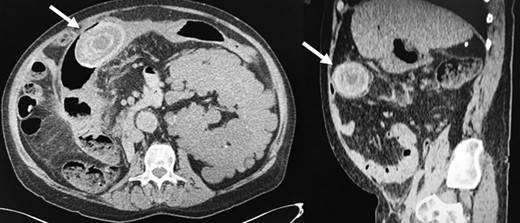

The patient presented to the ER complaining of abdominal pain, vomiting, and one abundant bloody diarrhea. His abdomen was distended with diffuse tenderness on physical examination. His vital signs were unremarkable except for a heart rate at 115/min. An abdominopelvic CT scan was performed, and showed a CCF with the giant 5 × 7 cm2 gallstone in the proximal transverse colon (Fig. 2). Oral contrast did not reveal any cholecystoduodenal communication. Blood tests revealed the following: white blood count 11.8 × 109/L, hemoglobin 145 g/L, creatinine 786 μmol/L, international normalized ratio (INR) 2.71 and normal alanine transaminase, aspartate transaminase, bilirubin, alkaline phosphatase and lipase.

Giant gallstone located in the proximal transverse colon on abdominopelvic CT scan.